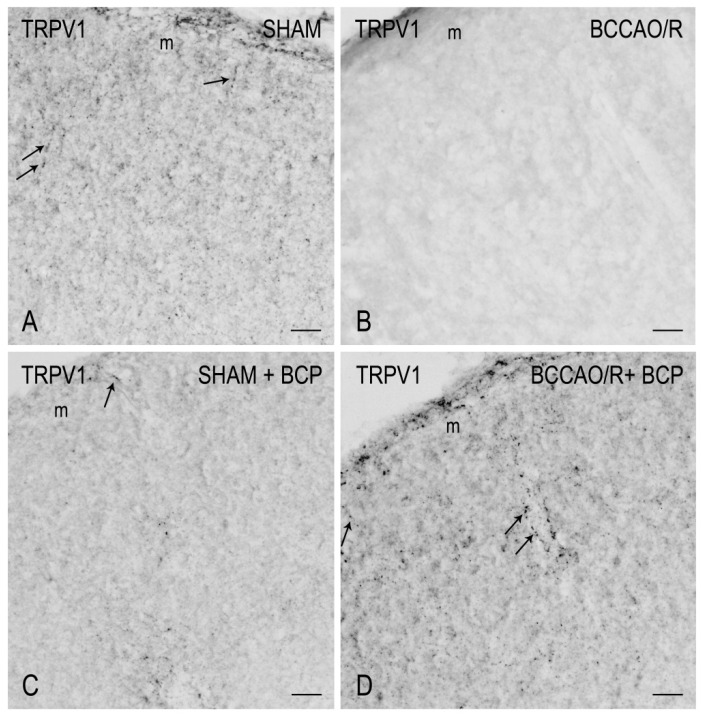

To draw a parallel of the molecular changes observed by Western blot analysis with the tissue morphology, we performed immunostainings of the rat brain sections with the same antibodies used for Western Blot analysis. Immunoreactivities for all examined markers were localized to neuronal structures distributed throughout the rostro-caudal extension of the brain (Figure 3, Figure 4, Figure 5 and Figure 6). As regards the frontal cortex, TRPV1-LI appeared as sparse dot-like elements and tiny varicose nerve fibers distributed mostly close to blood vessels or around them (Figure 3 and Figure 6A,D,G). Neuronal perikarya showing a faint intracytoplasmic staining with a dust-like aspect were further detectable (Figure 6A,D). Labeling of the meningeal lining of the cortex was also detectable. By contrast with the scarcity of TRPV1-LI, the BDNF- and trkB-like immunoreactive structures were numerous and identifiable as neuronal perikarya and proximal processes and nerve fibers distributed throughout the cortical layers, having the aspect of loose networks of thin filaments and punctate elements in the superficial layers, and straight neuronal processes with a prevalent radial orientation in the deep layers (Figure 4 and Figure 5). Double labeling for either TRPV1 and GFAP (astrocyte marker) or TRPV1 and Iba1 (microglia marker), carried out by means of indirect immunofluorescence in selected series of brain sections from BCCAO/R rats showed that, in both BCP- and vehicle-treated rats, rare TRPV1-labelled nerve fibers and dot-like elements were also GFAP-immunoreactive (Figure 6C,F), whereas TRPV1/Iba1 colocalization was virtually absent (Figure 6B).

3.2. TRPV1-like Immunoreactive Structures in BCCAO/R with and without BCP

The TRPV1 expression in the CNS has been investigated in numerous previous studies using different techniques; however, the available information concerning its cellular localization and regional distribution is still contradictory [ref. 48,ref. 49,ref. 71,ref. 72,ref. 73,ref. 74,ref. 75,ref. 76]. On the other hand, there is consensus regarding the involvement of TRPV1 in functions that, on the base of its multimodal activation, differ depending on the neuronal system/neuropathological condition considered [ref. 50,ref. 77].

Similar to available studies on the distribution of TRPV1-LI in the rodent CNS [ref. 49,ref. 50], our results show that TRPV1 occurs in the frontal cortex where it localizes to cell bodies, mainly with an intracytoplasmic distribution, and dot- and thread-like elements suggestive of nerve fibers. However, at variance with previous studies [ref. 49,ref. 50], in our hands, the cortical TRPV1-labeling was light (under baseline and BCP-treated BCCAO/R conditions) to virtually absent (in BCCAO/R condition after vehicle-treatment) and, when present, the TRPV1-positive structures often underlined the course of some blood vessels in the cortex. It remains to clarify whether the vessel-associated immunoreactive elements we observed are genuine nerve fibers, as suggested by their varicose appearance, or stand for non-nervous vascular elements as shown by transmission electron microscopy (TEM) in the rat brain [ref. 49]. TRPV1 mRNA has also been reported in several other vascular beds in the rat [ref. 76,ref. 78]. Interestingly, the TRPV1 on sensory nerve terminals mediates local vasodilation, while the vascular TRPV1 leads to vasoconstriction [ref. 76]. Cavanaugh and coll [ref. 76] suggested that, in thermoregulatory tissues, activation of TRPV1 on vascular smooth muscle cells could counteract nerve-related changes in vascular tone in response to physiological TRPV1 agonists. Provided that a diverging role for TRPV1 was also possible in the brain vessels, it could be speculated that the TRPV1 increase induced by BCP in BCCAO/R compared to sham rats is partly involved in controlling the homeostasis of the cortical vascular bed under the reperfusion challenge.

This last inferring is further supported by our findings that after the BCP-treatment, beyond the TRPV1 increase, significant GFAP downregulation and partial TRPV1-/GFAP-like immunoreactivity colocalization were detectable in the BCCAO/R compared to the vehicle-treated rats. While the evaluation of GFAP expression in our setting warrants further investigations to clarify the astroglial involvement in the regulation of TRPV1 relative levels in the brain after BCCAO/R, it is tempting to hypothesize that the TRPV1-bearing astrocytes may be contributing to the regulation of vascular tone under the hypoperfusion/reperfusion challenge. Interestingly, TRPV1-positive astrocytes have already been demonstrated in the rat spinal cord [ref. 79] and brain [ref. 49]. As already suggested [ref. 49], astrocytes may represent another critical element by which TRPV1 may intervene to regulate the vascular bed, either by modulating the tone of cerebral vessels or modulating the blood-brain barrier permeability in response to an inflammatory challenge. Indeed, though with a time longer than that of our BCCAO/R model, it has been shown that the inflammatory milieu generated by 2.5 h of ischemic brain injury stimulated a strong astroglial response. This response was featured by cell hypertrophy and hyperplasia [ref. 77,ref. 80], and it was suggested that it may lead to an increased expression of GFAP, partly because the number of GFAP-positive astrocytes increases [ref. 81].